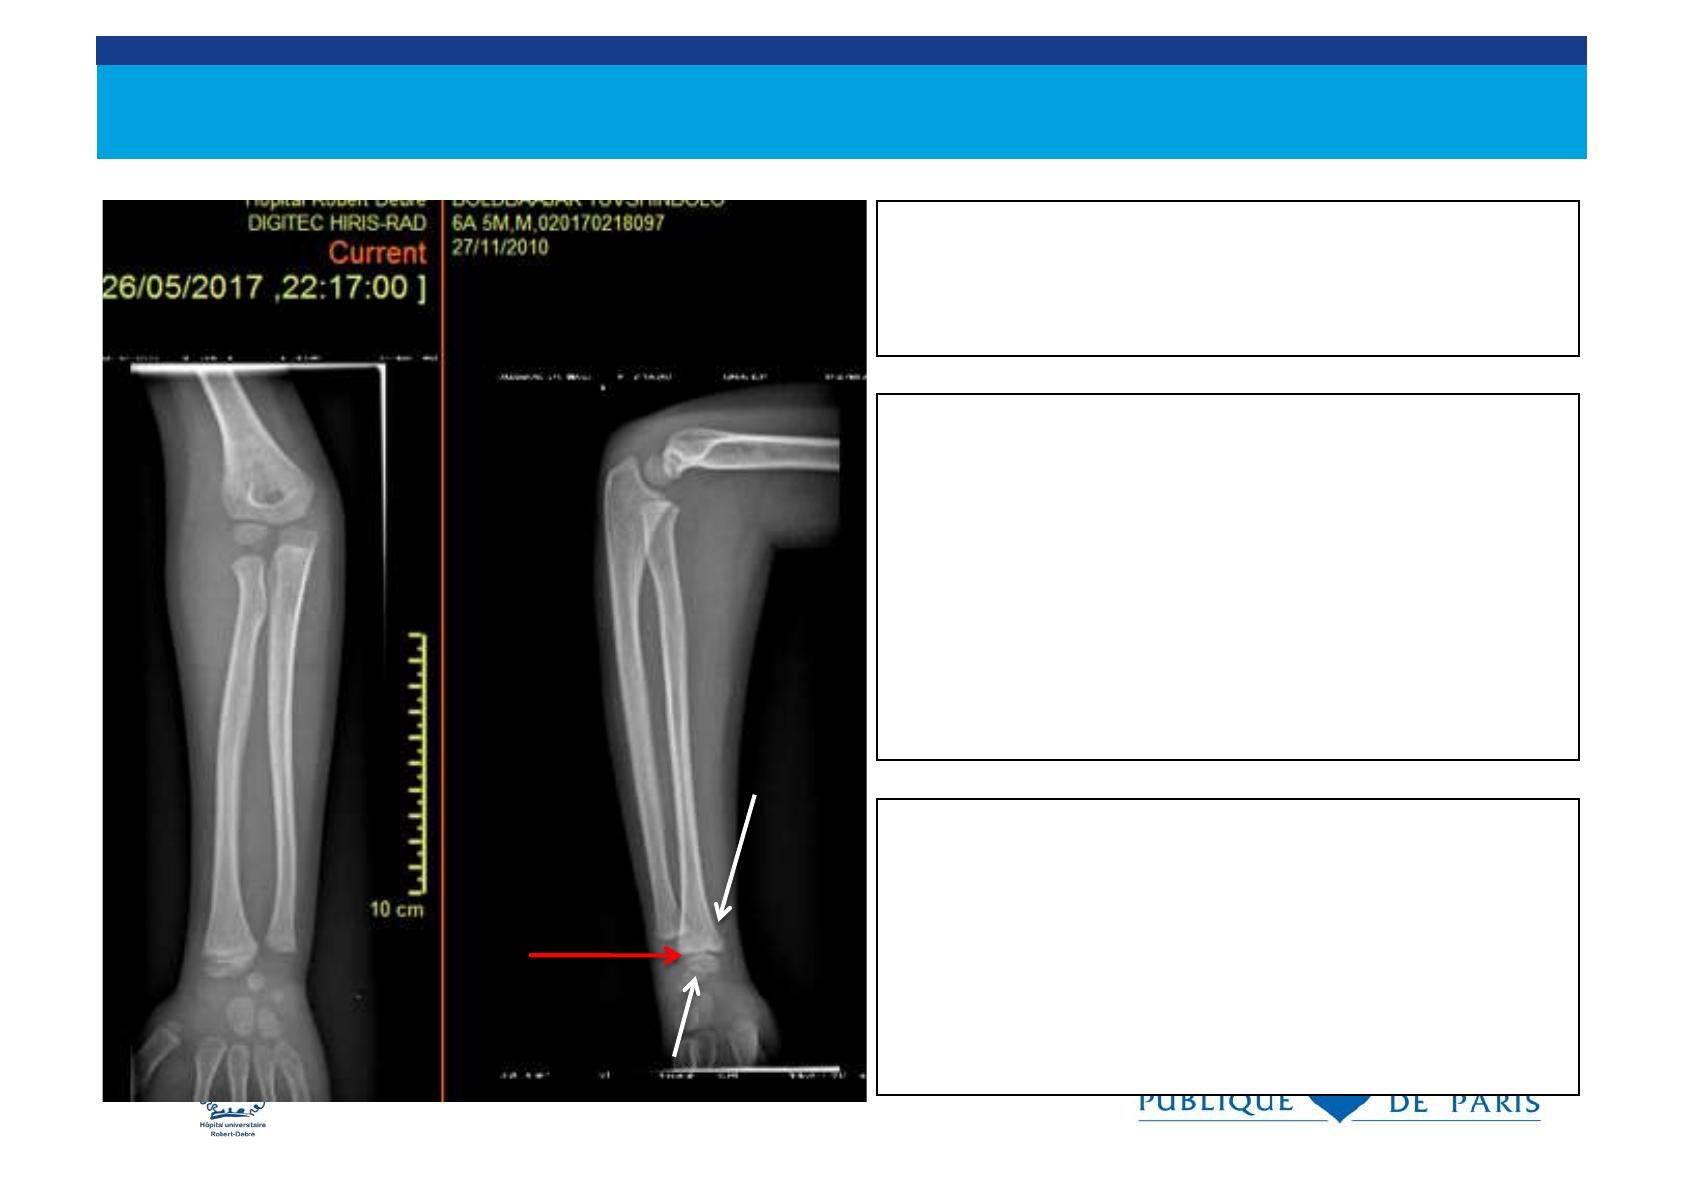

Le cartilage de croissance

. sépare l’ épiphyse de la métaphyse et il est

radiotransparent

. les fractures peuvent traverser le cartilage de

croissance.

. Les traumatismes du cartilage de croissance

déterminent le pronostic des fractures de l’ enfant

métaphyse

épiphyse

cartilage de croissance